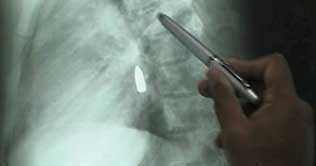

Doctors at Pakistan Institute of Medical Sciences (PIMS) have miraculously removed a bullet from the heart of a youth.A youth identified as 29-year-old Asif Jhanjua was hit by bullet on his chest that penetrated into his heart. The bullet caused severe damage to three chambers of his heart, besides damaging one of his hearts pumping valves. Doctors at PIMS Hospital carried out a surgery of Asifs damaged heart chambers and successfully removed the bullet from his heart during an operation that lasted for four hours. Doctor Naveed talking to Dunya News termed the survival of the patient as a miracle and said that the operation was extremely complicated.